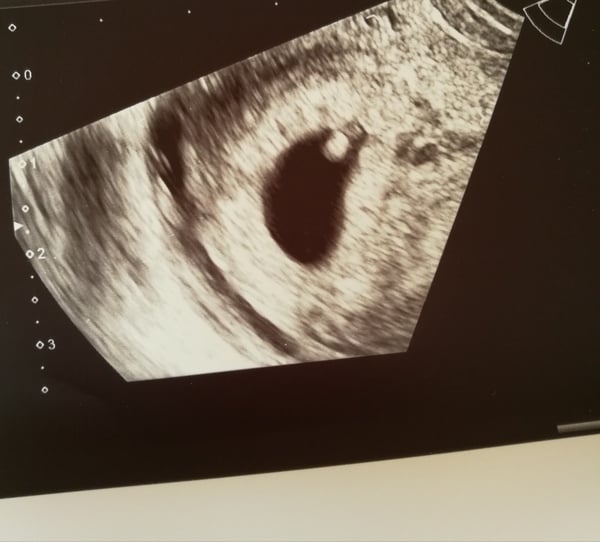

Hello all - update: had my scan yesterday, saw heartbeat, head, body, etc (I am 8 weeks along). Massively relieved, and further reassured by continuing nausea, though it does make work tricky.

They did not give me a printout of the scan... Sad Are we supposed to ask for one?

babayagga congratulations! So glad it went well. I got given a copy of mine automatically with the paperwork detailing dates and measurements etc. Did you sit down with a nurse after the scan?

Thattwat - they gave me a piece of paper with info, but no photograph. Extreme NHS austerity?.. I'll be sure to ask for one next time.

Definitely ask Babayagga! I had to ask what it all was so maybe they just felt sorry for me!

I asked for the photo...was told she wasn't supposed to give me one as there were others in the waiting room getting bad news, but she did and put it in an envelope and told me to put it in my bag till I got home...

EmilyK83 · 27/06/2017 21:38

I couldn't see much,but even this was a positive Smile

I think that's clearer than mine Emily! I was really Hmm when I saw mine as couldn't make it out at all. Can't wait for the 12 week when it looks a bit more baby like